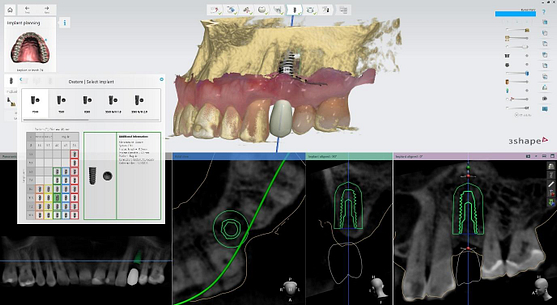

I utilized 3Shape Implant Studio, a module within the 3shape Unite Platform, to plan and execute the surgical procedure.

Pre-surgical planning began with acquiring high-quality diagnostic data, including TRIOS intraoral scans and CBCT imaging. The data was imported into 3Shape Implant Studio, where I designed a virtual crown for tooth 24 and planned the precise positioning of the implant, considering critical factors such as sinus proximity, adjacent roots, bone density, and the location of the bony defect.

A custom surgical guide was designed and 3D printed, incorporating all the critical information from the virtual planning. The implant surgery was performed under local anesthesia, with the surgical guide firmly in place to ensure accurate implant placement. Bone grafting was performed to address the bony defect and promote optimal healing.

The Osstem OneGuide kit is used with a fully guided osteotomy and implant placement.

Osstem TSIII D4 x H10mm implant on NoMount driver.